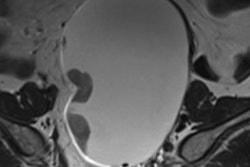

Dr. Christiane Kuhl on breast MRI.